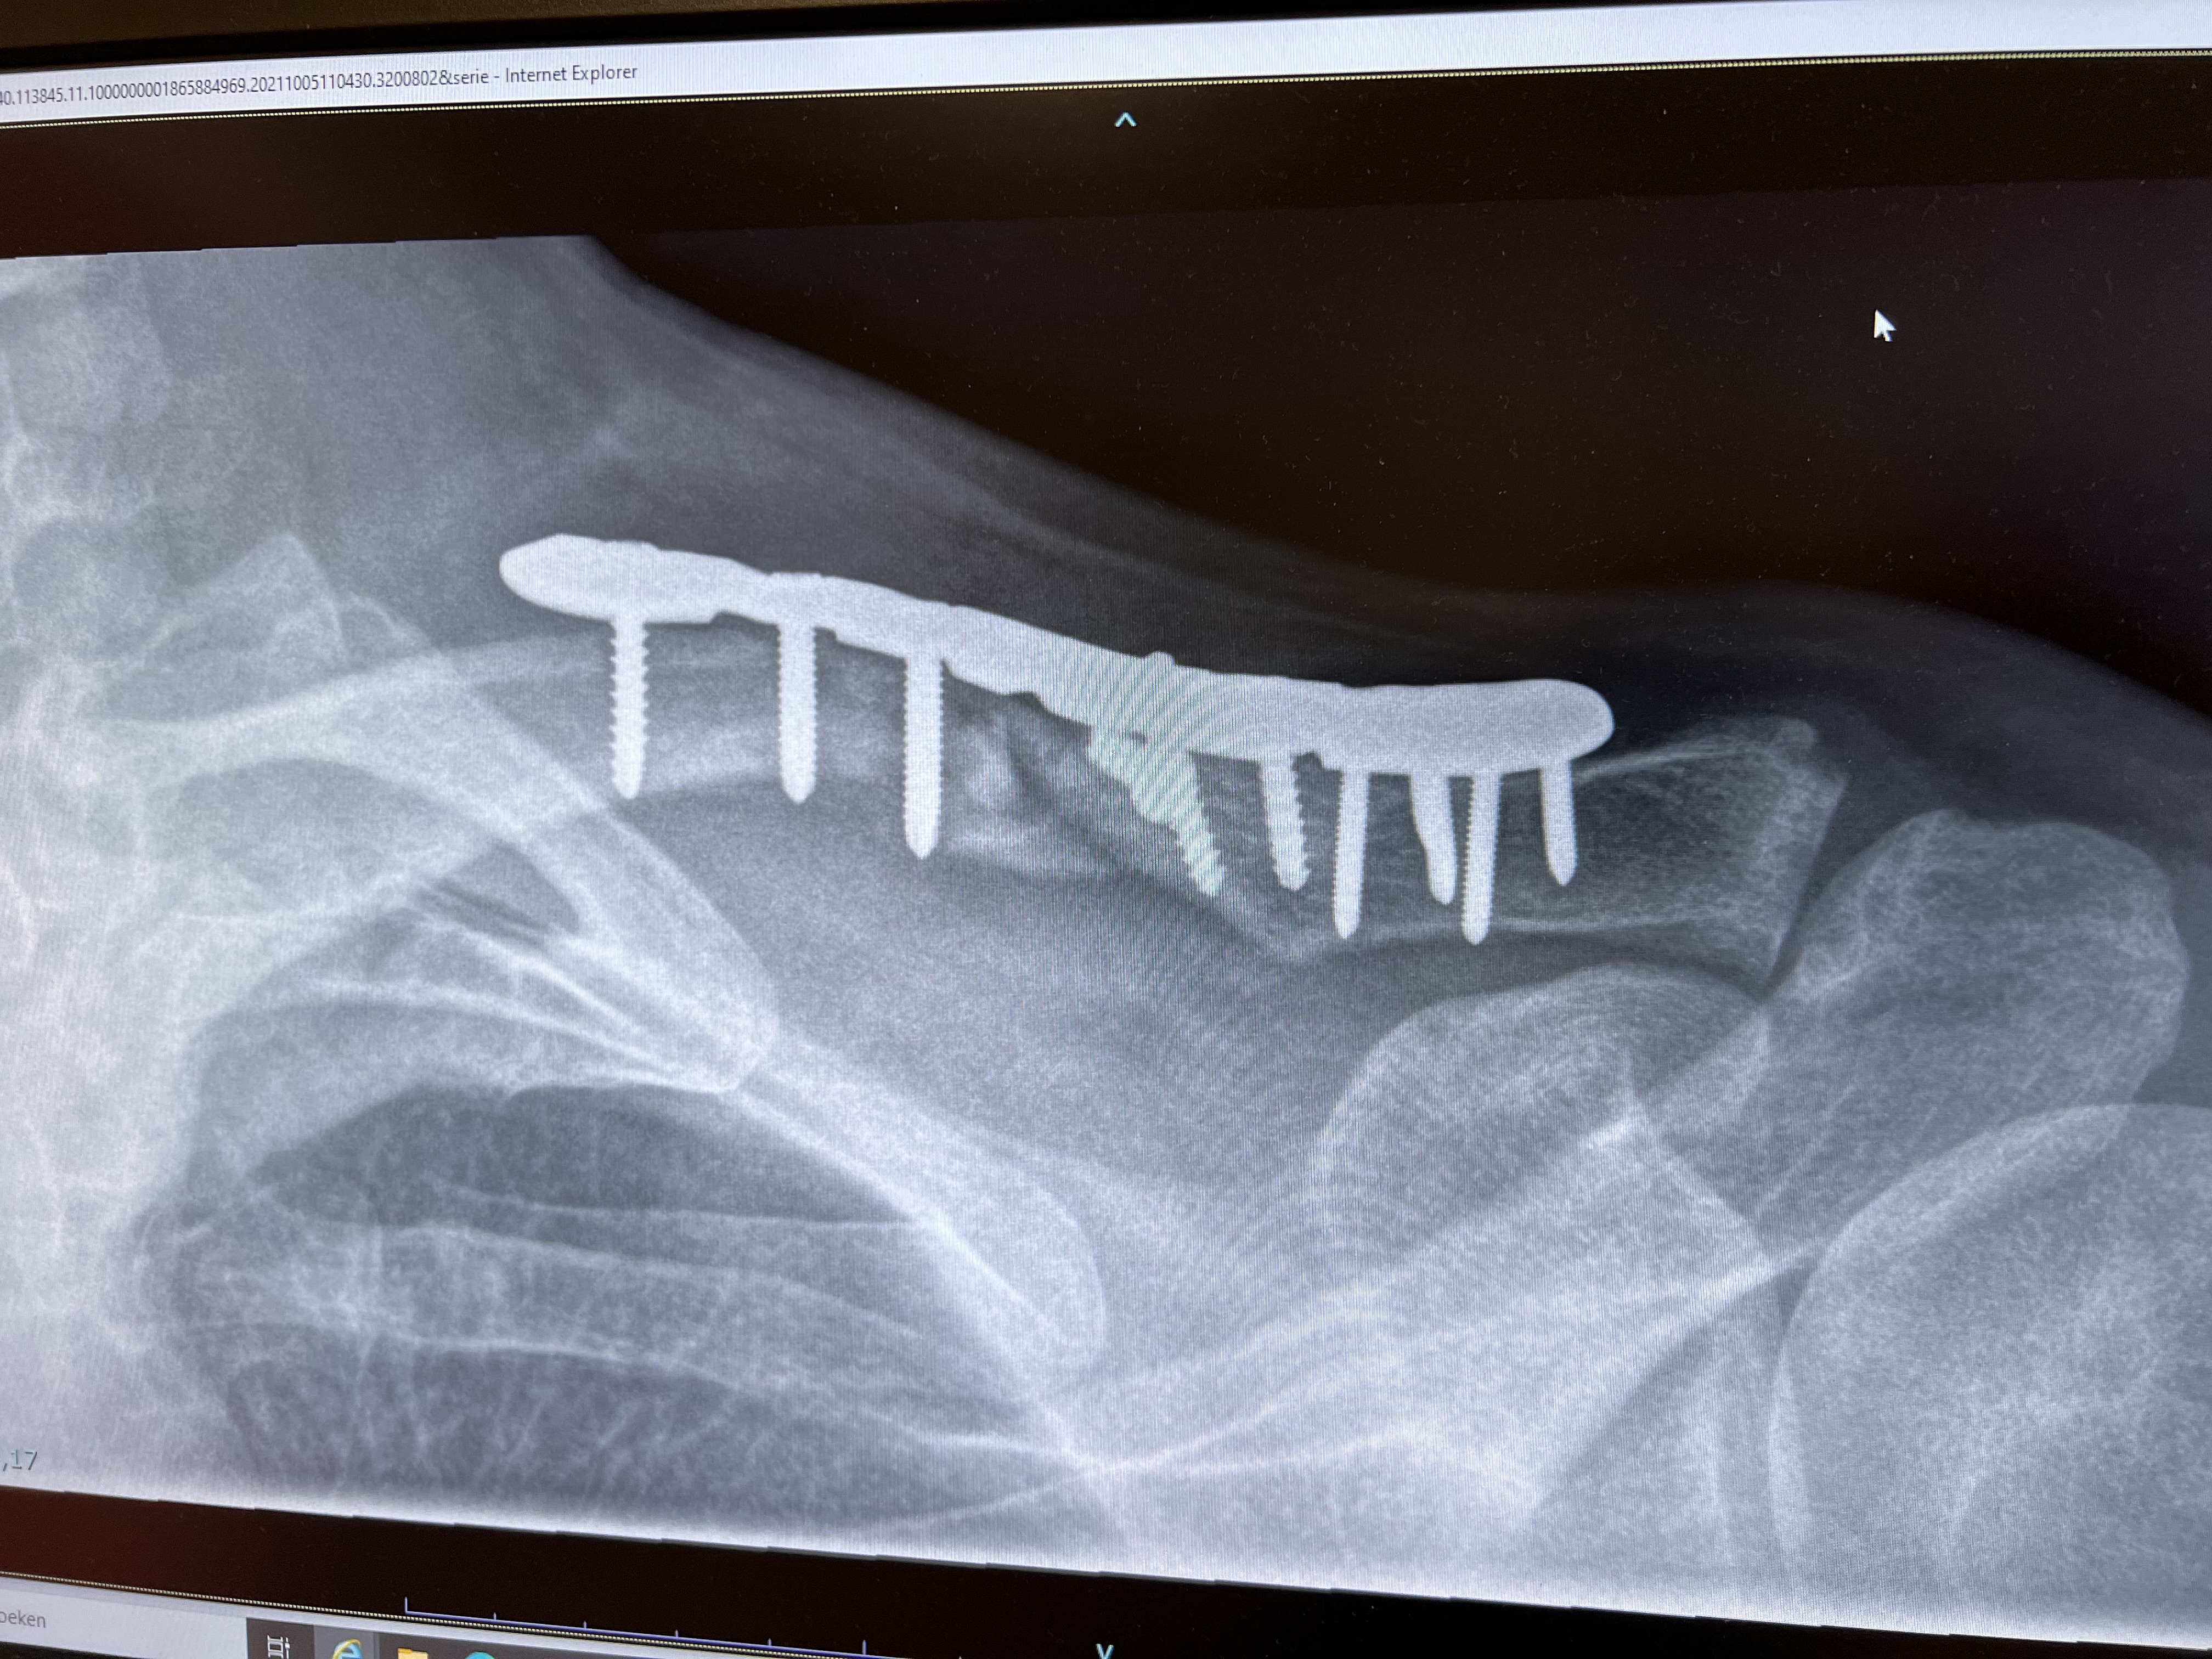

Mocht u nou denken, daar zit een schroefje los...

...dan klopt dat. Wellicht meegekregen via Twitter of Nieuwe Revu (want de tijdsgeest heeft ook mij ingehaald dus ik van het we-weblog dat altijd in stijlvol koninklijk meervoud schrijft, schrijf ook steeds meer in ik), maar mijn sleutelbeen is in september in duizend stukjes gefietst. En dat geneest helaas niet lekker. Er zit een stuk titanium met tien schroeven in, waarvan er twee langzaam los laten. Leuk voor het foto-album, minder voor de nachtrust of de dagbesteding. Die twee links komen langzaam omhoog en dat is behoorlijk niet de bedoeling. 'Je moet rustiger aan doen', zei de dokter, nadat ik net vijf weken vakantie had gehad. HOE DAN?